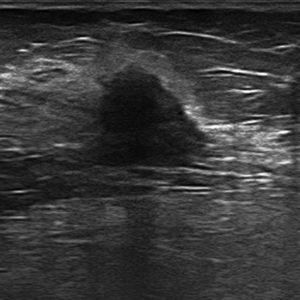

The most common mammographic finding of all is a mass-like lesion (45 per cent); other less common patterns are microcalcifications, with or without a solid component, and focal asymmetries.43 In the ultrasound, and in most of the cases, it usually appears as a hypoechogenic irregular lesion of microlobulated or angular edges, without posterior acoustic findings, with an abrupt interphase43 (Fig. 3). In the magnetic resonance imaging (MRI) it usually presents as one lesion of irregular morphology, although it may look round or oval and show irregular edges, hypointensity or isointensity in the T2-weighted sequences, heterogeneous internal enhancement, and dynamic behaviour in plateau or with washout.40,44

Luminal BIts average incidence is around 15 per cent.39 Initially its survival rates at 5 years were around 40 per cent.35 In the images its traits are not different from the traits of luminal A-type neoplasms.